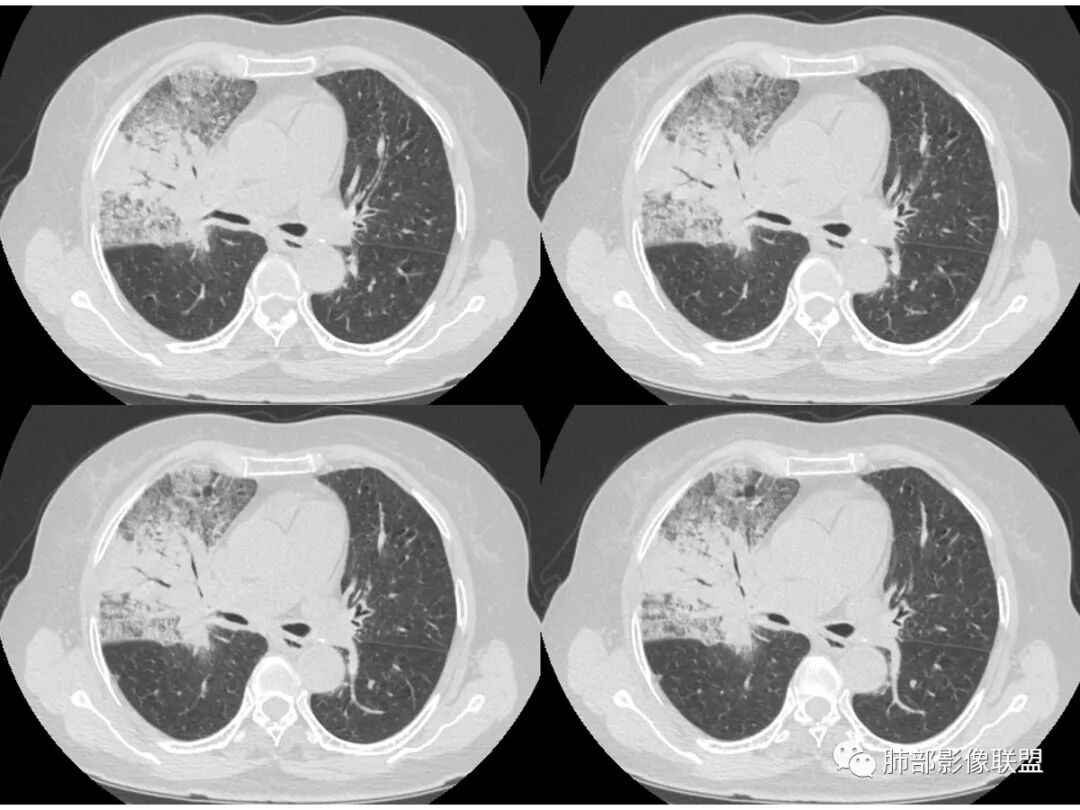

胸CT:右肺上叶实变内可见支气管充气征,近端支气管狭窄,远端扩张,周围可见毛玻璃影,右肺中叶支气管闭塞,并可见气道壁钙化,右肺中叶体积缩小,实变内可见空洞,并可见气液平面,空洞周围可见毛玻璃样影,右肺下叶支气管开口狭窄,右肺门淋巴结肿大。纵隔窗可见病灶与壁层胸膜间隙增宽,考虑良性病变-----感染性病变------TB?

右中叶支气管完全阻塞伴厚壁空洞,右上叶支气管不全阻塞伴大片GGN,右下部分GGN考虑腺鳞癌,结核待排。

老年女性,慢性病程,咳嗽伴白色粘液痰,无发热腹痛,糖尿病,白细胞及C反应蛋白不高,血沉快,铁蛋白高。胸部CT,右肺上叶大片状实变伴磨玻璃密度影,边界不清,边缘局部膨隆,叶裂弧形下坠,实变影宽基底与胸膜相贴;右肺下叶前基底段见类似病灶;右肺中叶不张并空洞形成,空洞内见气液平面;综合考虑右肺上叶及下叶肺炎型肺癌,右肺中叶结核。

老年女性,病史1月,右肺上中叶大片状影,跨叶,上叶为主,磨玻璃为主,边界模糊,部分实变,内见空洞影和液气平面,壁光滑,支气管开口狭窄,局部有扩张,右肺门淋巴结钙化,首先考虑感染性病变,结核可能,鉴别粘液腺癌。

老年女性,亚急性起病,右肺上中叶大片状影,跨叶,上叶为主,磨玻璃为主,边界模糊,部分实变,内见空洞影和液气平面,壁光滑,洞内可见结节形成,局部有扩张,首先考虑感染性病变,结核可能;洞内可见结节样病灶,鉴别合并曲霉、肿瘤。

这里是中叶的不张和空洞,有钙化,结核确实也不能排除

主病灶应该是粘腺腺癌,右中叶不张?,内空洞,壁光滑,考虑感染

1.王老师的病理说明粘液腺癌的破坏力弱,对血管和支气管破坏少,所以理论上空洞少,这个空洞很明确。

2.南大理论:粘液腺癌起源于外周,所以主体病灶位于胸膜下多见,这个病人主体病灶位于中心,外周磨玻璃为主,部分磨玻璃模糊

中叶的体积缩小,也不是粘液腺癌能完全解释,